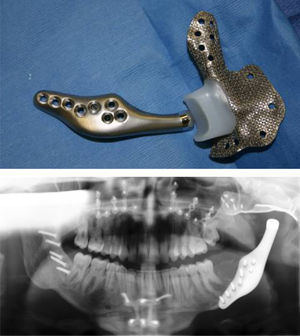

The most important principle in TMJ TJR surgery must be the stability of the device components at implantation. In orthopaedic surgery, some TJR devices can be initially stabilized by press-fitting or cementation into the cancellous shaft of the host long bone. However, the anatomy of the TMJ itself, mandibular ramus and the temporal glenoid fossa do not allow those options. Therefore, initial fixation and stabilization of all present TMJ TJR device fossa and ramus/condyle components must be provided by screws (Fig. 1).

Custom TMJ TJR fossa and ramal components screw fixated (TMJ Concepts, Ventura, CA). Commercially pure titanium (CP Ti) mesh fossa backing for UHMWPE articulating surface with posterior stop; wrought alloyed titanium (Ti–6Al–4V) ramus component and wrought Co–Cr–Mb articulating condylar head.

Custom TMJ TJR devices are “made to fit”. The components can be designed and manufactured to conform and manage any unique anatomical situation (Fig. 3). At implantation, neither the components nor the host bone require alteration, augmentation or supplementation to achieve initial overall component-to-host bone stability maximizing the prospect for fixation screw osseointegration. This results in screw fixation that secures the custom TMJ TJR device components to the host bone, mitigating the potential for micromotion and is responsible for the long-term reported stability and function of custom TMJ replacement devices.34–37

The custom TMJ TJR device with the most published studies in refereed literature is manufactured using commercially pure titanium (CP Ti) as the fossa backing for UHMWPE articulating surface; wrought alloyed titanium (Ti–6Al–4V) for the ramus component and wrought Co–Cr–Mb for the articulating condylar head (Fig. 1).